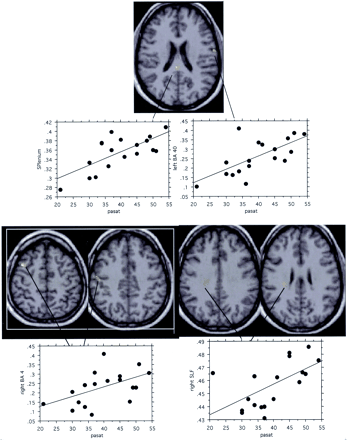

Correlation Between Brain MTR Decrease and MSFC Score

Significant correlations between MTR and MSFC scores (Spearman rank test, P < .05) were observed in patients in the left BA40, right SLF, right frontal white matter, splenium, and projection of the anterior corpus callosum (Fig 3 and Table 4).

In patients with CISSMS, significant correlations between MTR and MSFC scores (Spearman rank test, P < .05) are observed inside right SLF (FLS), right frontal white matter (WM), projections of the anterior corpus callosum (CC), splenium, and left BA40 (left to right).

Correlation Between Brain MTR Decrease and PASAT Score

Significant correlations between MTR and PASAT scores (Spearman rank test, P < .05) were observed in patients in the left BA40, right BA4, right SLF, and splenium (Fig 4 and Table 4).

In patients with CISSMS, significant correlations between MTR and PASAT scores (Spearman rank test, P < .05) are observed in the splenium, left BA40, right BA 4, and right SLF.